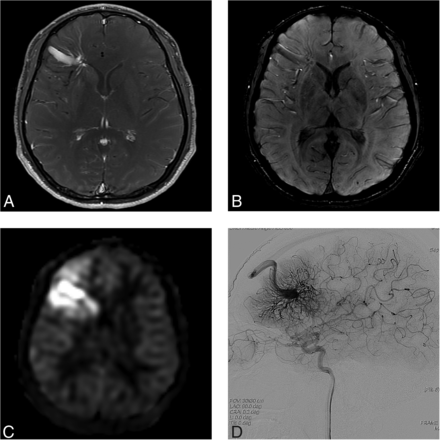

A 29-year-old man presenting with an AVM in the left occipital lobe (case 11). A, Contrast-enhanced T1-weighted axial MR imaging shows a DVA-like lesion in the right frontal lobe. B, SWI shows hypointense signal in the lesion. C, An ASL quantitative CBF image demonstrates no identifiable signal corresponding to the lesion. D, On DSA, the lesion is first visualized in the late venous phase (arrows), as is typically seen in a classic DVA.